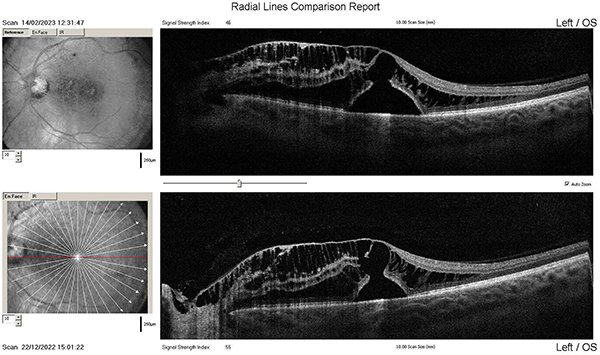

Paciente de sexo femenino de 38 años, sin antecedentes patológicos generales, con antecedentes de cirugía refractiva (LASIK) de ojo derecho de excelente resultado. Consultó un año después de la intervención por disminución brusca e indolora de la AV de OI. El examen oftalmológico inicial era: AVMC OD 10/10 sc OI 4/10 nmcc (ARM OI +1,00 -0,75 x 176°), BMC y PIO sin particularidades en ambos ojos, FO OD retina aplicada y OI edema macular y alteración periférica de pigmento. Realizamos OCT donde observamos líquido subretinal con esquisis de capas internas de la retina y pérdida marcada de la depresión foveal (fig. 12). Lo interpretamos inicialmente como evento vascular oclusivo y procedimos a inyección intravítrea de anti-VEGF e interconsulta con cardiología y hematología. El control tras la inyección de bevacizumab no mostró buena respuesta clínica ni en OCT. A los dos meses le realizamos la segunda inyección intravítrea, el control posterior mostró AVMC OI 3/10 (+0,75) y en OCT persistía el engrosamiento macular a expensas de la retinosquisis y aumento del LSR (fig. 13). Reevaluamos y reinterpretamos el caso como pit de papila asociado a desprendimiento seroso. Procedimos a la cirugía: VPP con PMLI y aposición de flap sobre el pit, taponamiento con hexafluoruro de azufre y endofotocoagulación. El control posterior a la cirugía mostró mejoría: AVMC OI 4/10 y en la OCT observamos disminución del espesor macular central con menos LSR (fig. 14) y flap posicionado sobre la papila (fig. 15). La paciente se encuentra en seguimiento periódico.

Figura 12. OCT de ojo izquierdo con desprendimiento seroso del neuroepitelio a nivel foveal y retinosquisis que afecta extensamente la mácula.

Figura 13. OCT de control de ojo izquierdo donde se observa empeoramiento de las lesiones iniciales.

Figura 14. OCT postoperatoria de ojo izquierdo que muestra disminución del desprendimiento seroso y retinosquisis.

Figura 15. OCT postoperatoria de ojo izquierdo focalizada sobre el disco óptico donde se observa el flap de membrana limitante interna posicionado sobre él.